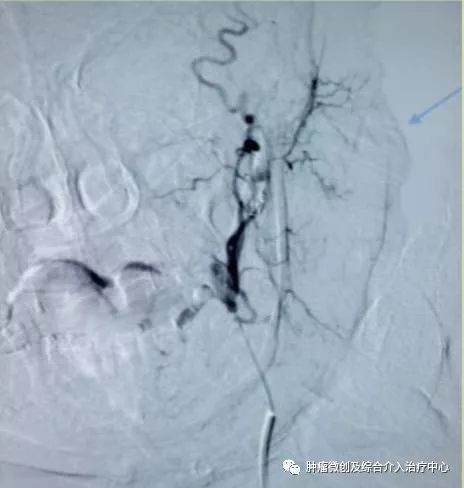

( DSA造影提示胃十二指肠分支血管出血)